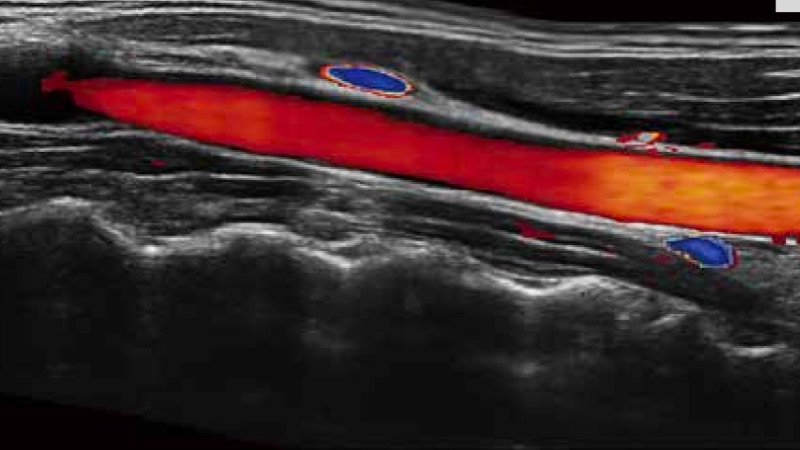

SR Flow高分辨率血流成像

高分辨率血流成像技术提高了对低速血流信号的检测能力。在提高空间分辨率的同时,也克服了血流外溢现象,为用户提供更加真实的血流动力学信息。

实时宽景成像技术

通过彩色血流和实时宽景相结合,可观察到完整的动静脉血流,方便医生检查。实时扫查过程中,如有任何操作失误也可以很容易地进行回扫擦除,而不会中断扫查。

临床图像